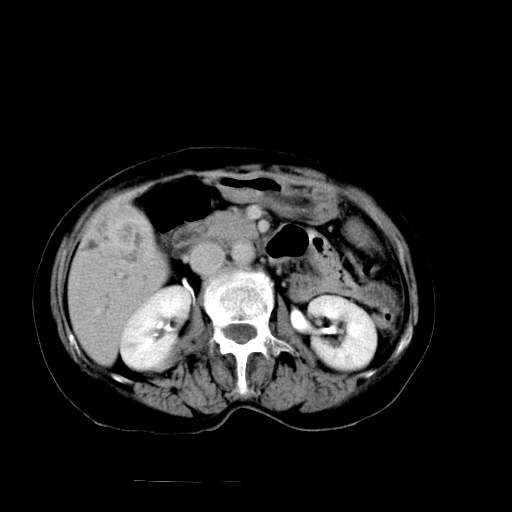

以下是引用卜一在2009-4-7 5:06:00的发言:[br]左右肝内胆管结石伴扩张合并胆系感染;不除外胆管细胞癌可能。支持! [br] [br]

以下是引用随光逐影在2009-4-7 8:21:00的发言:[br]肝内外胆管多发性结石并肝内外胆管扩张;胆系感染。